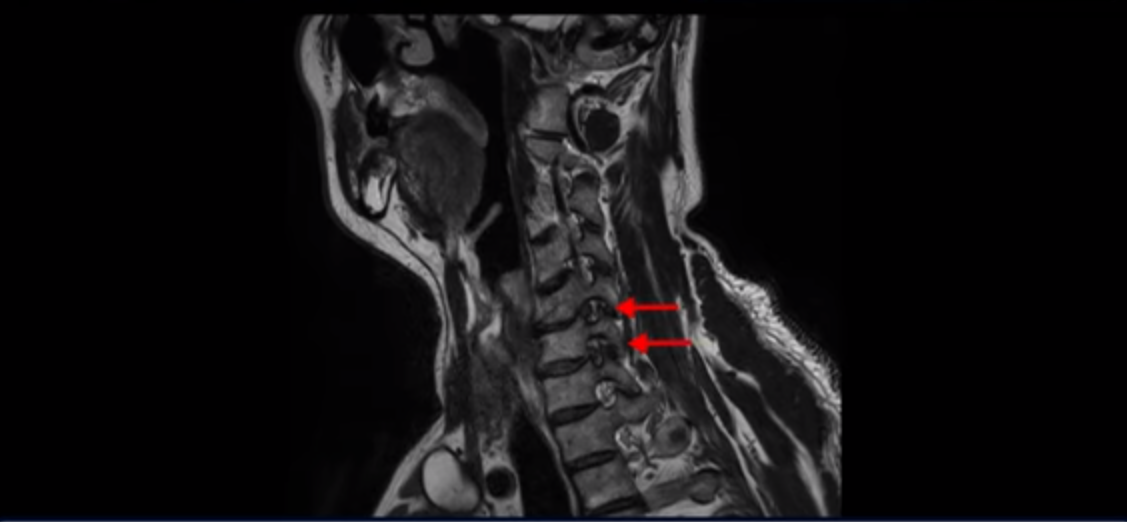

우선 이분 증상은 좌측 어깨와 팔 통증입니다. 이분 MRI를 보면 5번 6번과 6번 7번이 안 좋아 보입니다.

왼쪽으로 신경이 빠져나가는 추간공을 보면 보시다시피 5번 6번과 6번 7번 신경 구멍이 아래나 위에 비해 막혀있는 게 보입니다.

디스크도 밀려 나와 있고 협착도 있는 겁니다.

이분 왼쪽 어깨와 팔 통증이 갑자기 생긴 이유는 5번 6번 디스크 또는 6번 7번 디스크가 갑자기 밀려 나온 것이 원인일 것으로 보이는데, 그럼 이 디스크들이 밀려 나와서 신경을 자극하거나 누르는데 어떻게 이게 수술 없이도 좋아질 수 있는 걸까요?